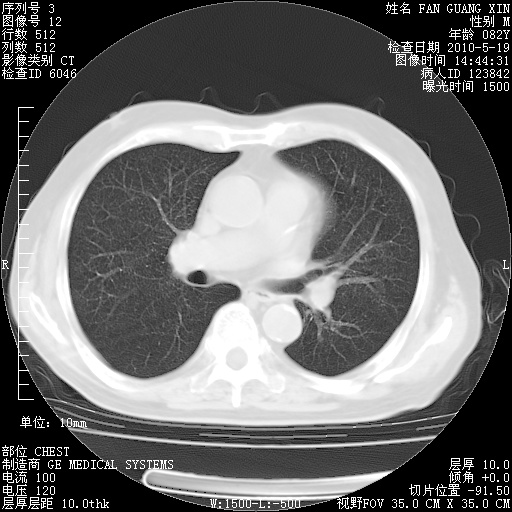

可改为口服强的松40-50mg/d治疗,若病情仍稳定,胸部阴影不再吸收可逐渐减量